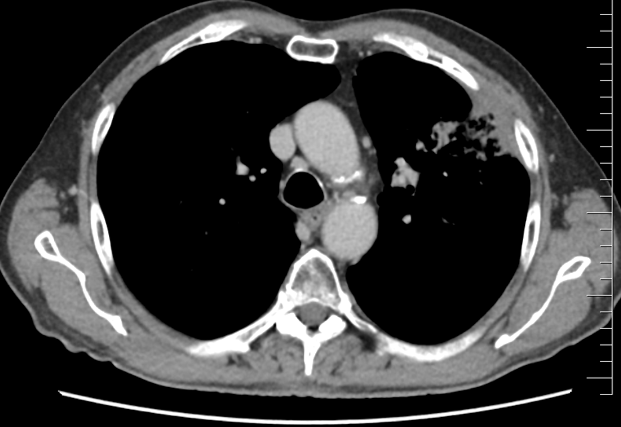

Do I. linie léčby byla indikována paliativní chemoterapie v režimu CBDCA/gemcitabin, cisplatina pro renální insuficienci a komorbidity nebyla možná. Dávka prednisonu snížena na 5mg. Léčba byla zahájena v 2/2021. Pro trombocytopenii G1 a neutropenii G3 byla nutná podpory růstovými faktory G-CFS a redukce dávek cytostatik až o 30%. Během léčby došlo postupně k regresi a vymizení lymfedemu dolních končetin. Na CT trupu v 5/2021 popsána regrese ložisek plic i uzlin v hilech plic. Po 6 sériích chemoterapie v 9/2021 ale dochází již k progresi jedno z plicních ložisek. V 11/2021 byla provedena paliativní RT na oblast metastatického postižení levé plíce v dávce 10x4Gy, vše bez komplikací.

Řez plicemi z CT screeningu: Kontrolní  CT plic před zahájením léčby pembrolizumabem v 10/2021

Obr 2. – Kontrolní  CT plic před zahájením léčby pembrolizumabem v 10/2021.